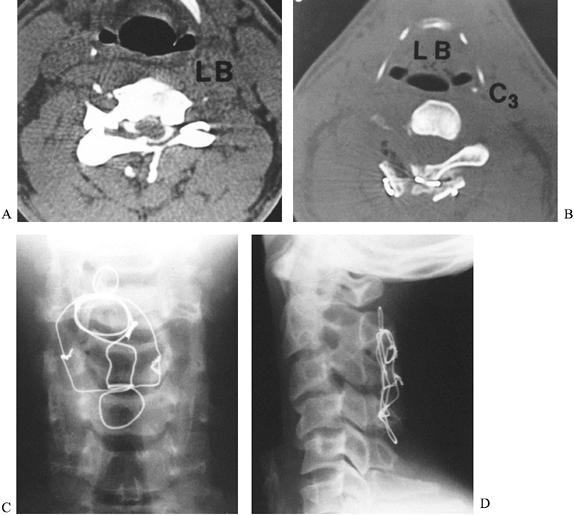

Figure 140.6. A:

Axial CT image of a 25-year-old man who sustained a diving injury. The patient has a fracture dislocation of the left C-3 facet joint. The inner aspect of the lamina is seen compressing the posterior aspect of the spinal cord. He had numbness on the left side of his neck in the C-3 nerve distribution. In addition, he was hyperreflexic throughout, secondary to a myelopathic lesion. B: The patient underwent a posterior decompression and triple-wire stabilization from C-2 to C-4. This axial postoperative CT image shows the posterior wiring and bone graft that stabilized the spine. Notice the adequacy of the decompression of the spinal canal. C: AP radiograph of the triple-wire stabilization technique from C-2 to C-4. The lateral wires hold two corticocancellous bone grafts in compression against the posterior aspects of the lamina at C-2 and C-4. D: Postoperative lateral radiograph shows a solid fusion from C-2 to C-4 with good spinal alignment aside from the patient’s original 15% subluxation at C3–C4. The patient was neurologically completely intact, and his spine was stable at long-term follow-up. |